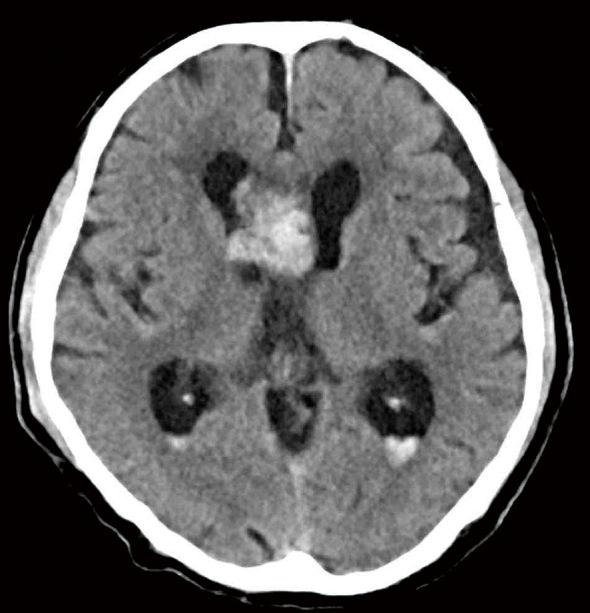

Subependymoma (SE) is a rare, usually asymptomatic, brain tumor predominantly affecting older adults and occurring in the fourth and lateral ventricles. We report a rare case of SE with intratumoral hemorrhage that could be removed by neuroendoscopy. The 81-year-old patient had been followed as an outpatient for 10 years due to an intraventricular tumor. It did not grow over the patient's lengthy follow-up. The patient was transferred to our hospital after he fainted near his home; at the time of admission, he had mild consciousness disturbance, and his Glasgow Coma Scale score was 10 points (E3V3M4). Computed tomography showed intratumoral hemorrhage and slight ventricular enlargement. Magnetic resonance (MR) imaging showed a 4 cm-sized tumor in the anterior horn of the right lateral ventricle. The lesion appeared as a mixed-intensity solid tumor and showed irregular enhancement with gadolinium. The patient underwent neuroendoscopic tumor resection on the 30 day of the patient's hospital stay. A histopathological examination revealed small tumor cells with round nuclei scattered in the glial fibrillary background. Immunostaining was positive for glial fibrillary acidic protein; these findings are consistent with an SE diagnosis. The patient in this study had hypertension and used anticoagulants, risk factors for intratumoral hemorrhage. For intraventricular tumors with bleeding-particularly in older or more physically frail patients-minimally invasive neuroendoscopic surgery should be considered an option for tumor resection.

室管膜下瘤(SE)是一种罕见的、通常无症状的脑肿瘤,主要影响老年人,多发生于第四脑室和侧脑室。我们报告一例罕见的伴有瘤内出血的室管膜下瘤,该肿瘤可通过神经内镜切除。这位81岁的患者因脑室内肿瘤已作为门诊患者随访了10年。在患者漫长的随访期间肿瘤未生长。患者在家附近晕倒后被转至我院;入院时,他有轻度意识障碍,格拉斯哥昏迷量表评分为10分(E3V3M4)。计算机断层扫描显示瘤内出血和轻度脑室扩大。磁共振成像显示右侧脑室前角有一个4厘米大小的肿瘤。该病变表现为混合密度实性肿瘤,钆增强扫描显示不规则强化。患者在住院第30天行神经内镜肿瘤切除术。组织病理学检查显示圆形核的小肿瘤细胞散在于胶质纤维背景中。免疫染色胶质纤维酸性蛋白呈阳性;这些发现符合室管膜下瘤的诊断。本研究中的患者患有高血压并使用抗凝剂,这些都是瘤内出血的危险因素。对于伴有出血的脑室内肿瘤,尤其是老年或身体较为虚弱的患者,微创神经内镜手术应被视为肿瘤切除的一种选择。